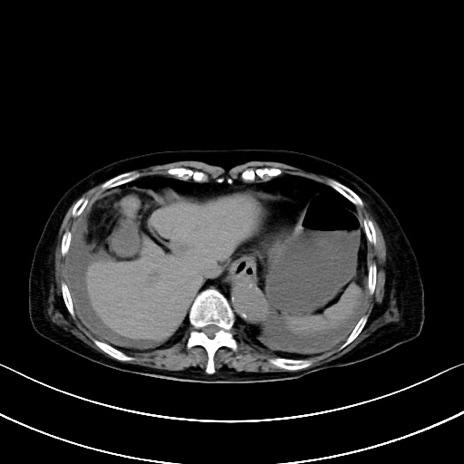

横断像

他院CT